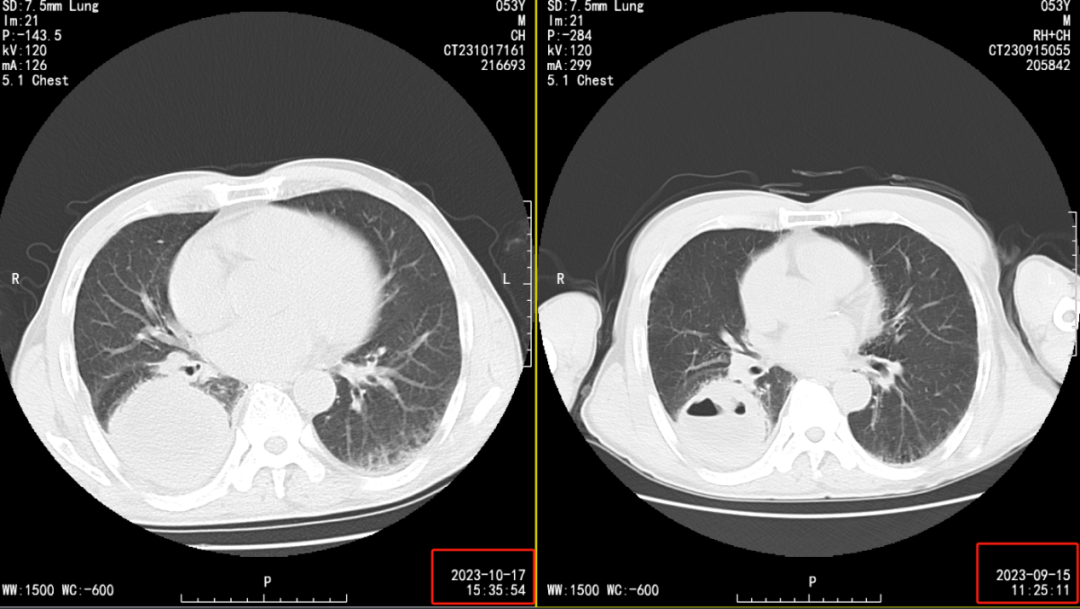

血源性多发性肺脓肿

图片尺寸823x516